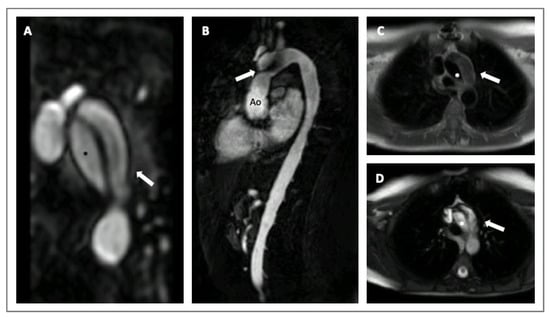

3. Genetics in HTADs

- Lenz, A.; Warncke, M.; Wright, F.; Weinrich, J.M.; Schoennagel, B.P.; Henes, F.O.; Adam, G.; von Kodolitsch, Y.; Schoen, G.; Bannas, P. Longitudinal follow-up by MR angiography reveals progressive dilatation of the distal aorta after aortic root replacement in Marfan syndrome. Eur. Radiol. 2023, 33, 6984–6992. [Google Scholar] [CrossRef]

- Evangelista, A.; Sitges, M.; Jondeau, G.; Nijveldt, R.; Pepi, M.; Cuellar, H.; Pontone, G.; Bossone, E.; Groenink, M.; Dweck, M.R.; et al. Multimodality imaging in thoracic aortic diseases: A clinical consensus statement from the European Association of Cardiovascular Imaging and the European Society of Cardiology working group on aorta and peripheral vascular diseases. Eur. Heart J. Cardiovasc. Imaging 2023, 24, e65–e85. [Google Scholar] [CrossRef] [PubMed]

- Steinbrecher, K.L.; Marquis, K.M.; Braverman, A.C.; Ohman, J.W.; Bhalla, S.; Lin, C.Y.; Naeem, M.; Raptis, C.A. Imaging of Genetic Thoracic Aortopathy. Radiographics 2022, 42, 1283–1302. [Google Scholar] [CrossRef]